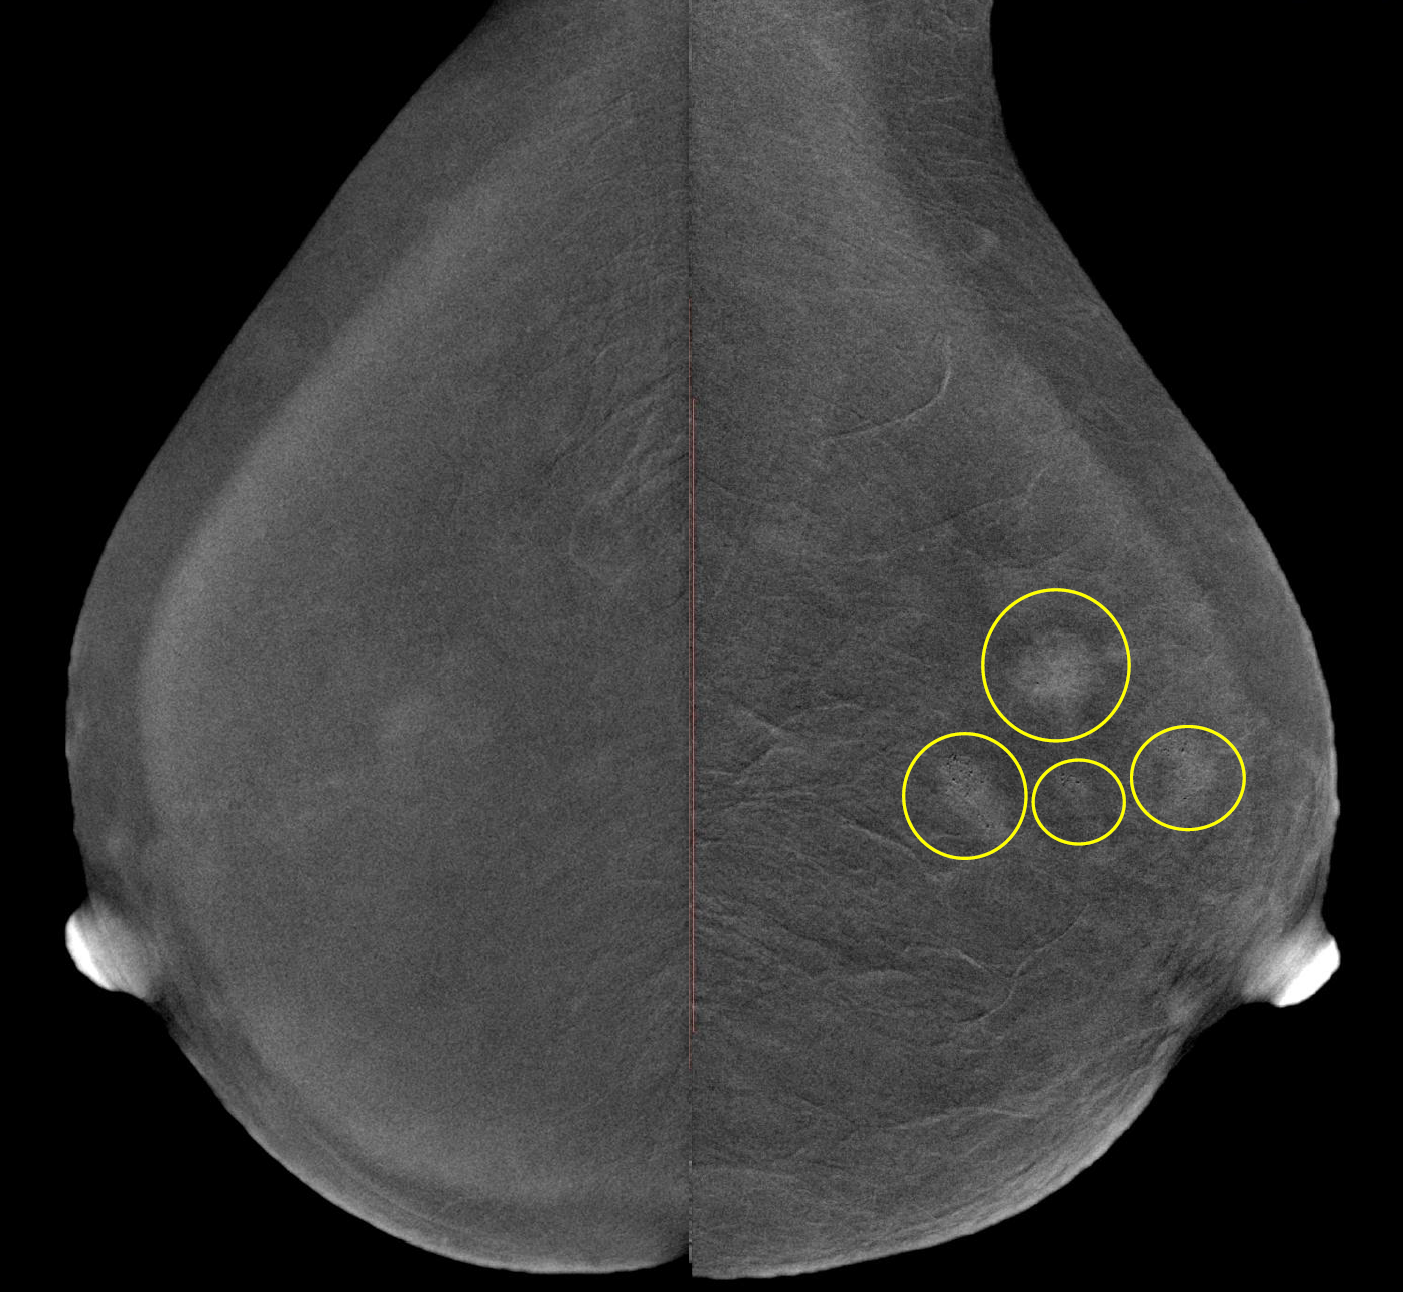

Метод прицельной маммографии с увеличением применяется для более детального исследования определенной области молочной железы. Он отличается высокой точностью диагностики. В отличие от обычной маммографии, которая предоставляет более общую информацию о состоянии молочных желез, прицельная маммография с увеличением позволяет получить точные данные о процессах, происходящих в тканях, благодаря методу компрессии конкретного участка.